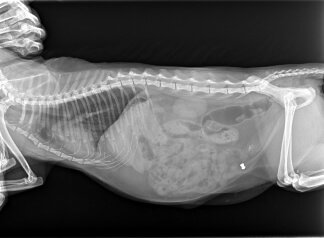

Ветеринар может рекомендовать 2 положения, как правило, на спине и на боку (правом или левом). Животное размещается на специальном столе или в аппарате (зависит от размеров и веса). С помощью рентгеновского излучения образуется изображение внутренних органов от диафрагмы до малого таза.

На снимке отчетливо видны инородные предметы из металла, полиэтилена, пластика, а также кусочки ткани. Иногда для получения более четкого силуэта органов вводится контрастное вещество, чаще всего бария сульфат. Лекарственное средство безопасно для животного.

Рентгенография брюшной полости собаки, кота позволяет увидеть внутренние органы, костные структуры, которые на снимке отображаются в виде светло-серых или белых четко очерченных пятен. У мягких тканей четких границ нет, но есть темно-серое очертание, поскольку они поглощают заметно меньше рентген-лучей.

Своевременно проведенная диагностика позволяет выявить травмы у животного, подтвердить прогрессирование желудочно-кишечных заболеваний, обнаружить непроходимость, отметить наличие увеличенных почек или печени, формирование камней в мочевом пузыре (частое осложнение у кастрированных питомцев).

При необходимости рентгенографию можно использовать для обследования беременных животных. Но только на позднем сроке. Для этого питомца укладывают в положении лежа на спине или на боку, что позволит определить количество плодов, наличие/отсутствие аномалий. Подобное исследование считается безопасным для мамы и ее детенышей.